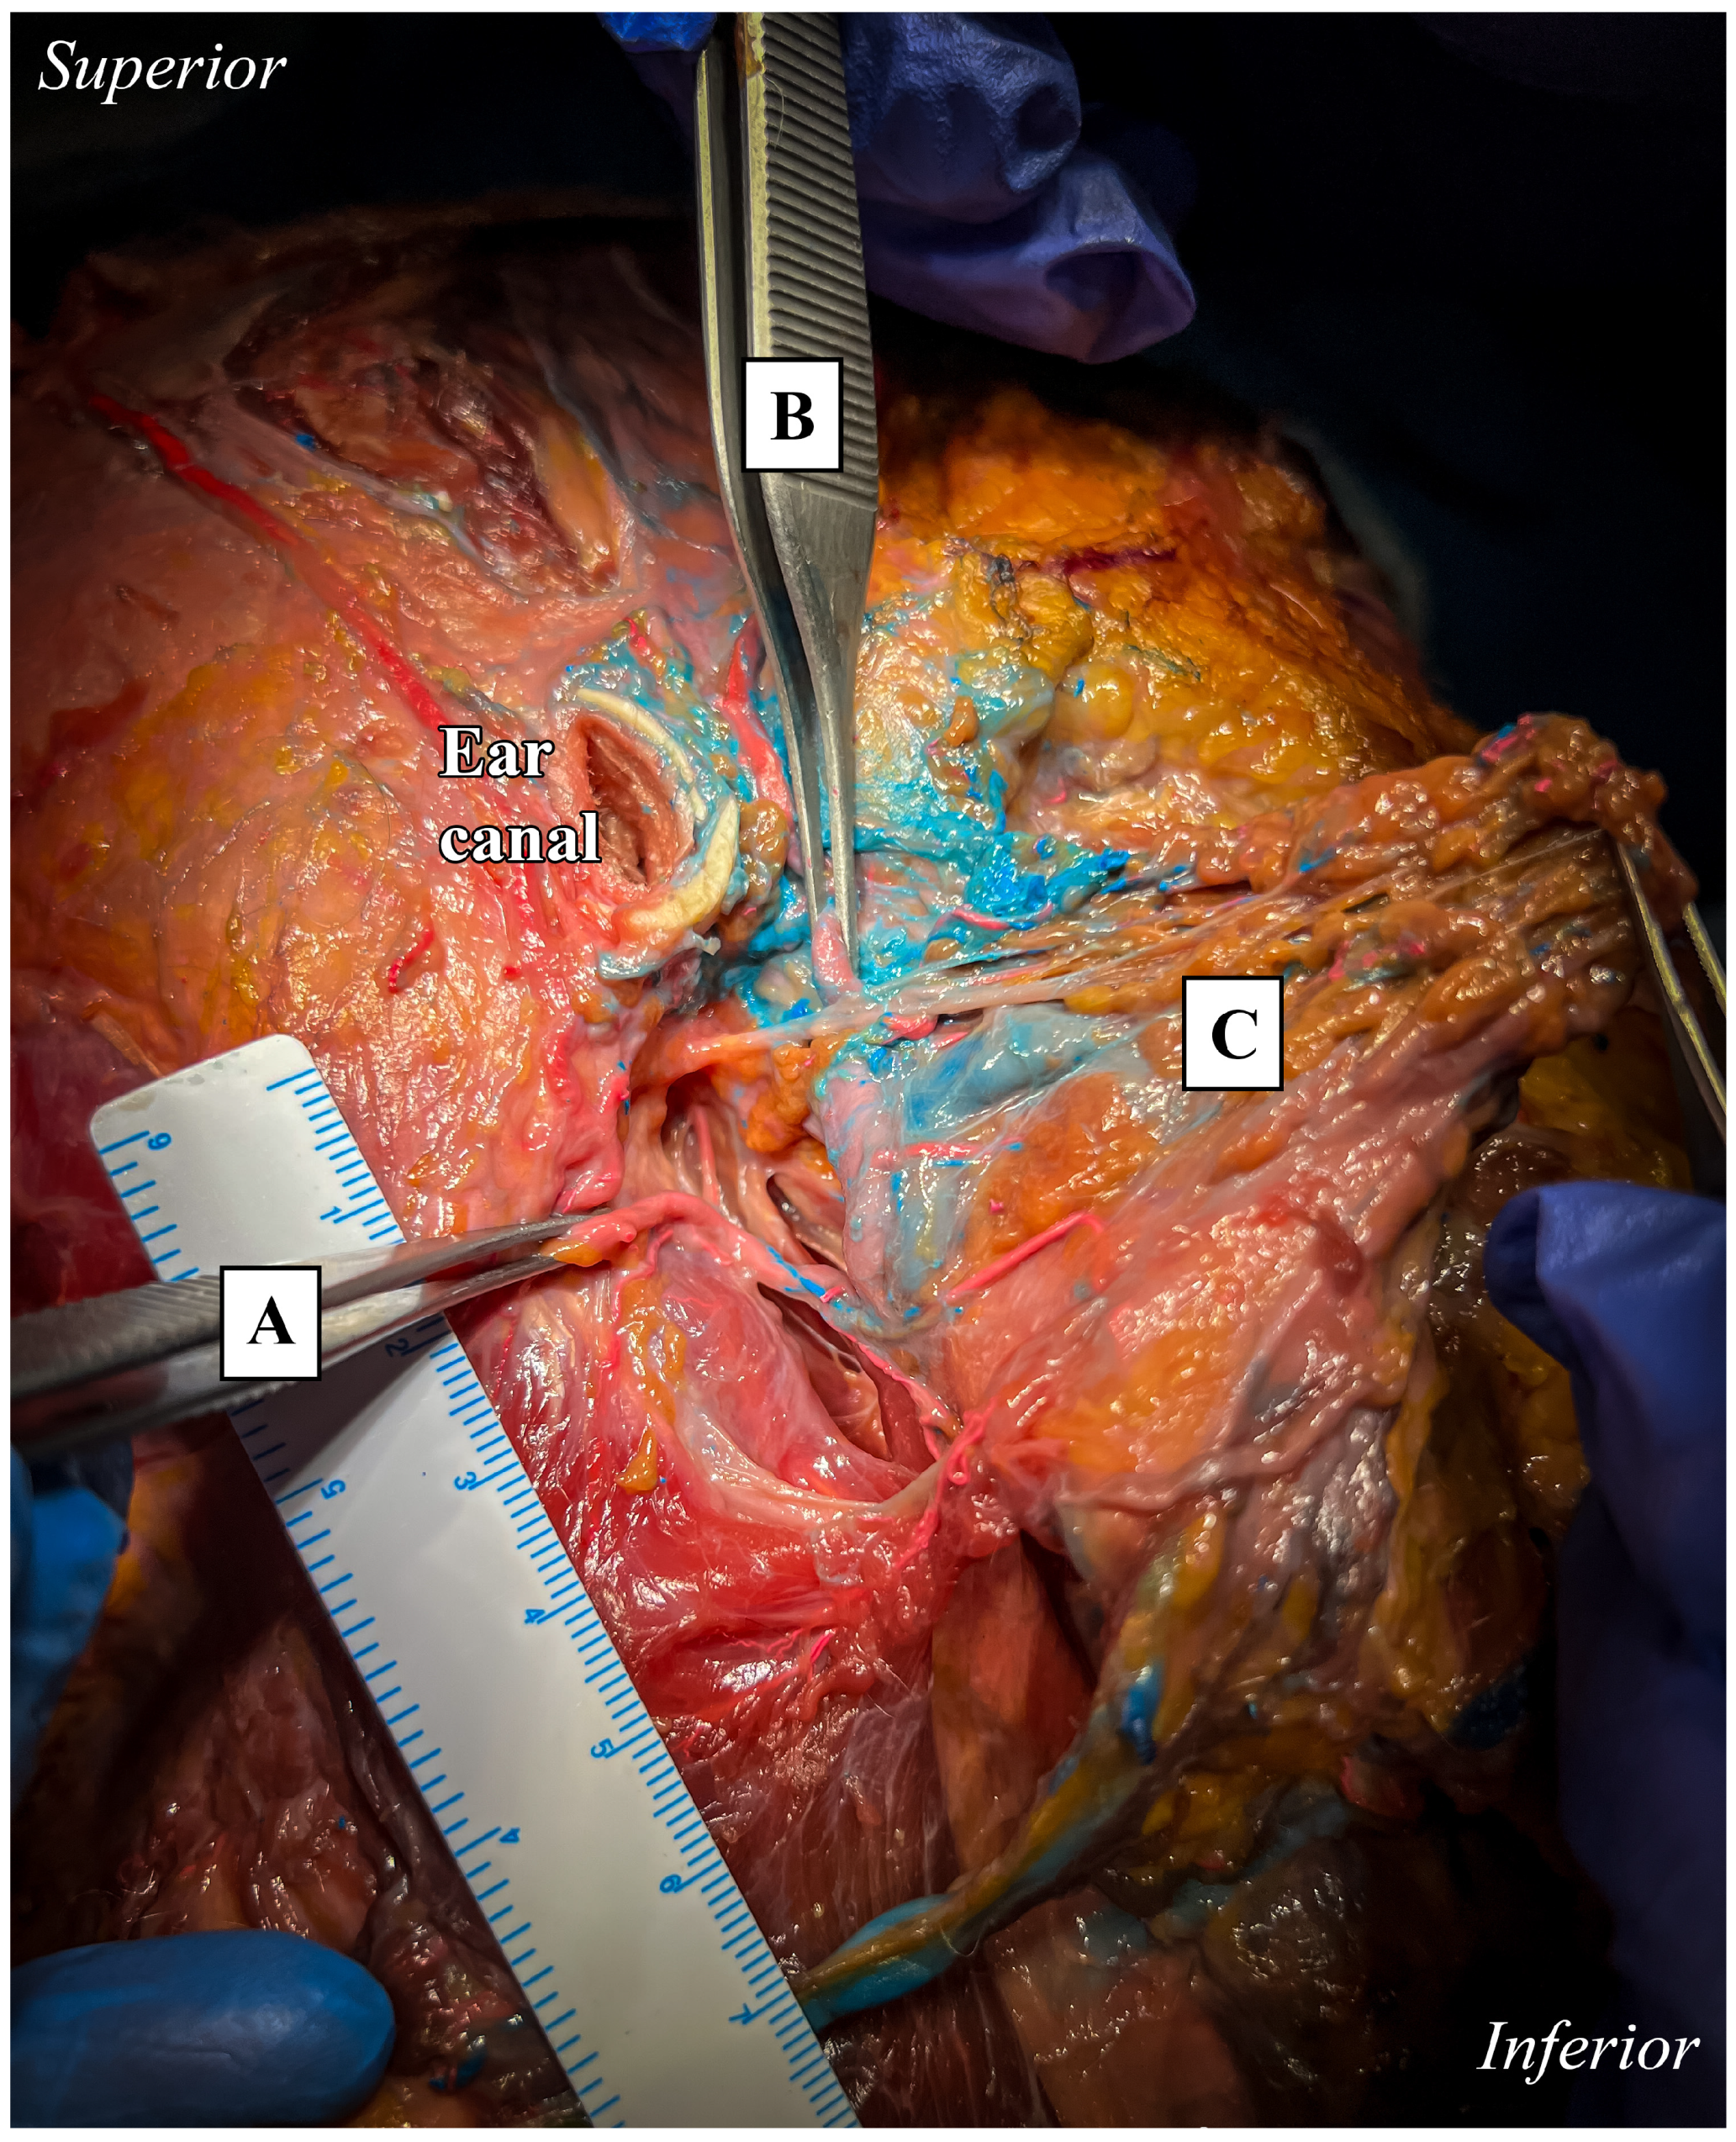

Once the STA had been identified and isolated anterior to the tragus, the course of the artery was followed distally and proximally to reveal its origin and branching pattern. The auricle was initially preserved for anatomical orientation (Figure 1) and then removed for better visualization (Figure 2).

Figure 1. Dissection of superficial layers with auricular pavilion in place. Lateral view of anatomical preparation. Temporal, infra-temporal, and parotid regions.